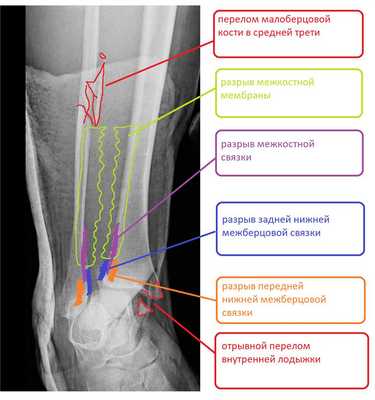

Клинический пример лечения разрыва дистального межберцового синдесмоза в нашей клинике.

Пациент Д.27 лет, травма в результате неудачного приземления после прыжка старзанки на мелководье. Стопа ушла кнаружи относительно фиксированной голени. Произошёл перелом малоберцовой кости в средней трети с разрывом всех компонентов дистального межберцового синдесмоза и отрывной перелом внутренней лодыжки.

Данный тип переломов лодыжек считается очень тяжёлым и относится к категории 44С2 по классификации Ассоциации Остеосинтеза. Казалось бы, сломаны всего 2 кости, да и переломы по своей морфологии не особо и тяжёлые, почему же данный тип переломов лодыжек считается крайне тяжёлым?

Всё дело в повреждении мягких тканей, прежде всего разрыве всех 4 компонентов дистального межберцового синдесмоза - передней и задней нижних межберцовых связок, межкостной связки и межкостной мембраны. Вместе с отрывом медиальной лодыжки всё это делает перелом абсолютно нестабильным и требует операции в 100% случаев.